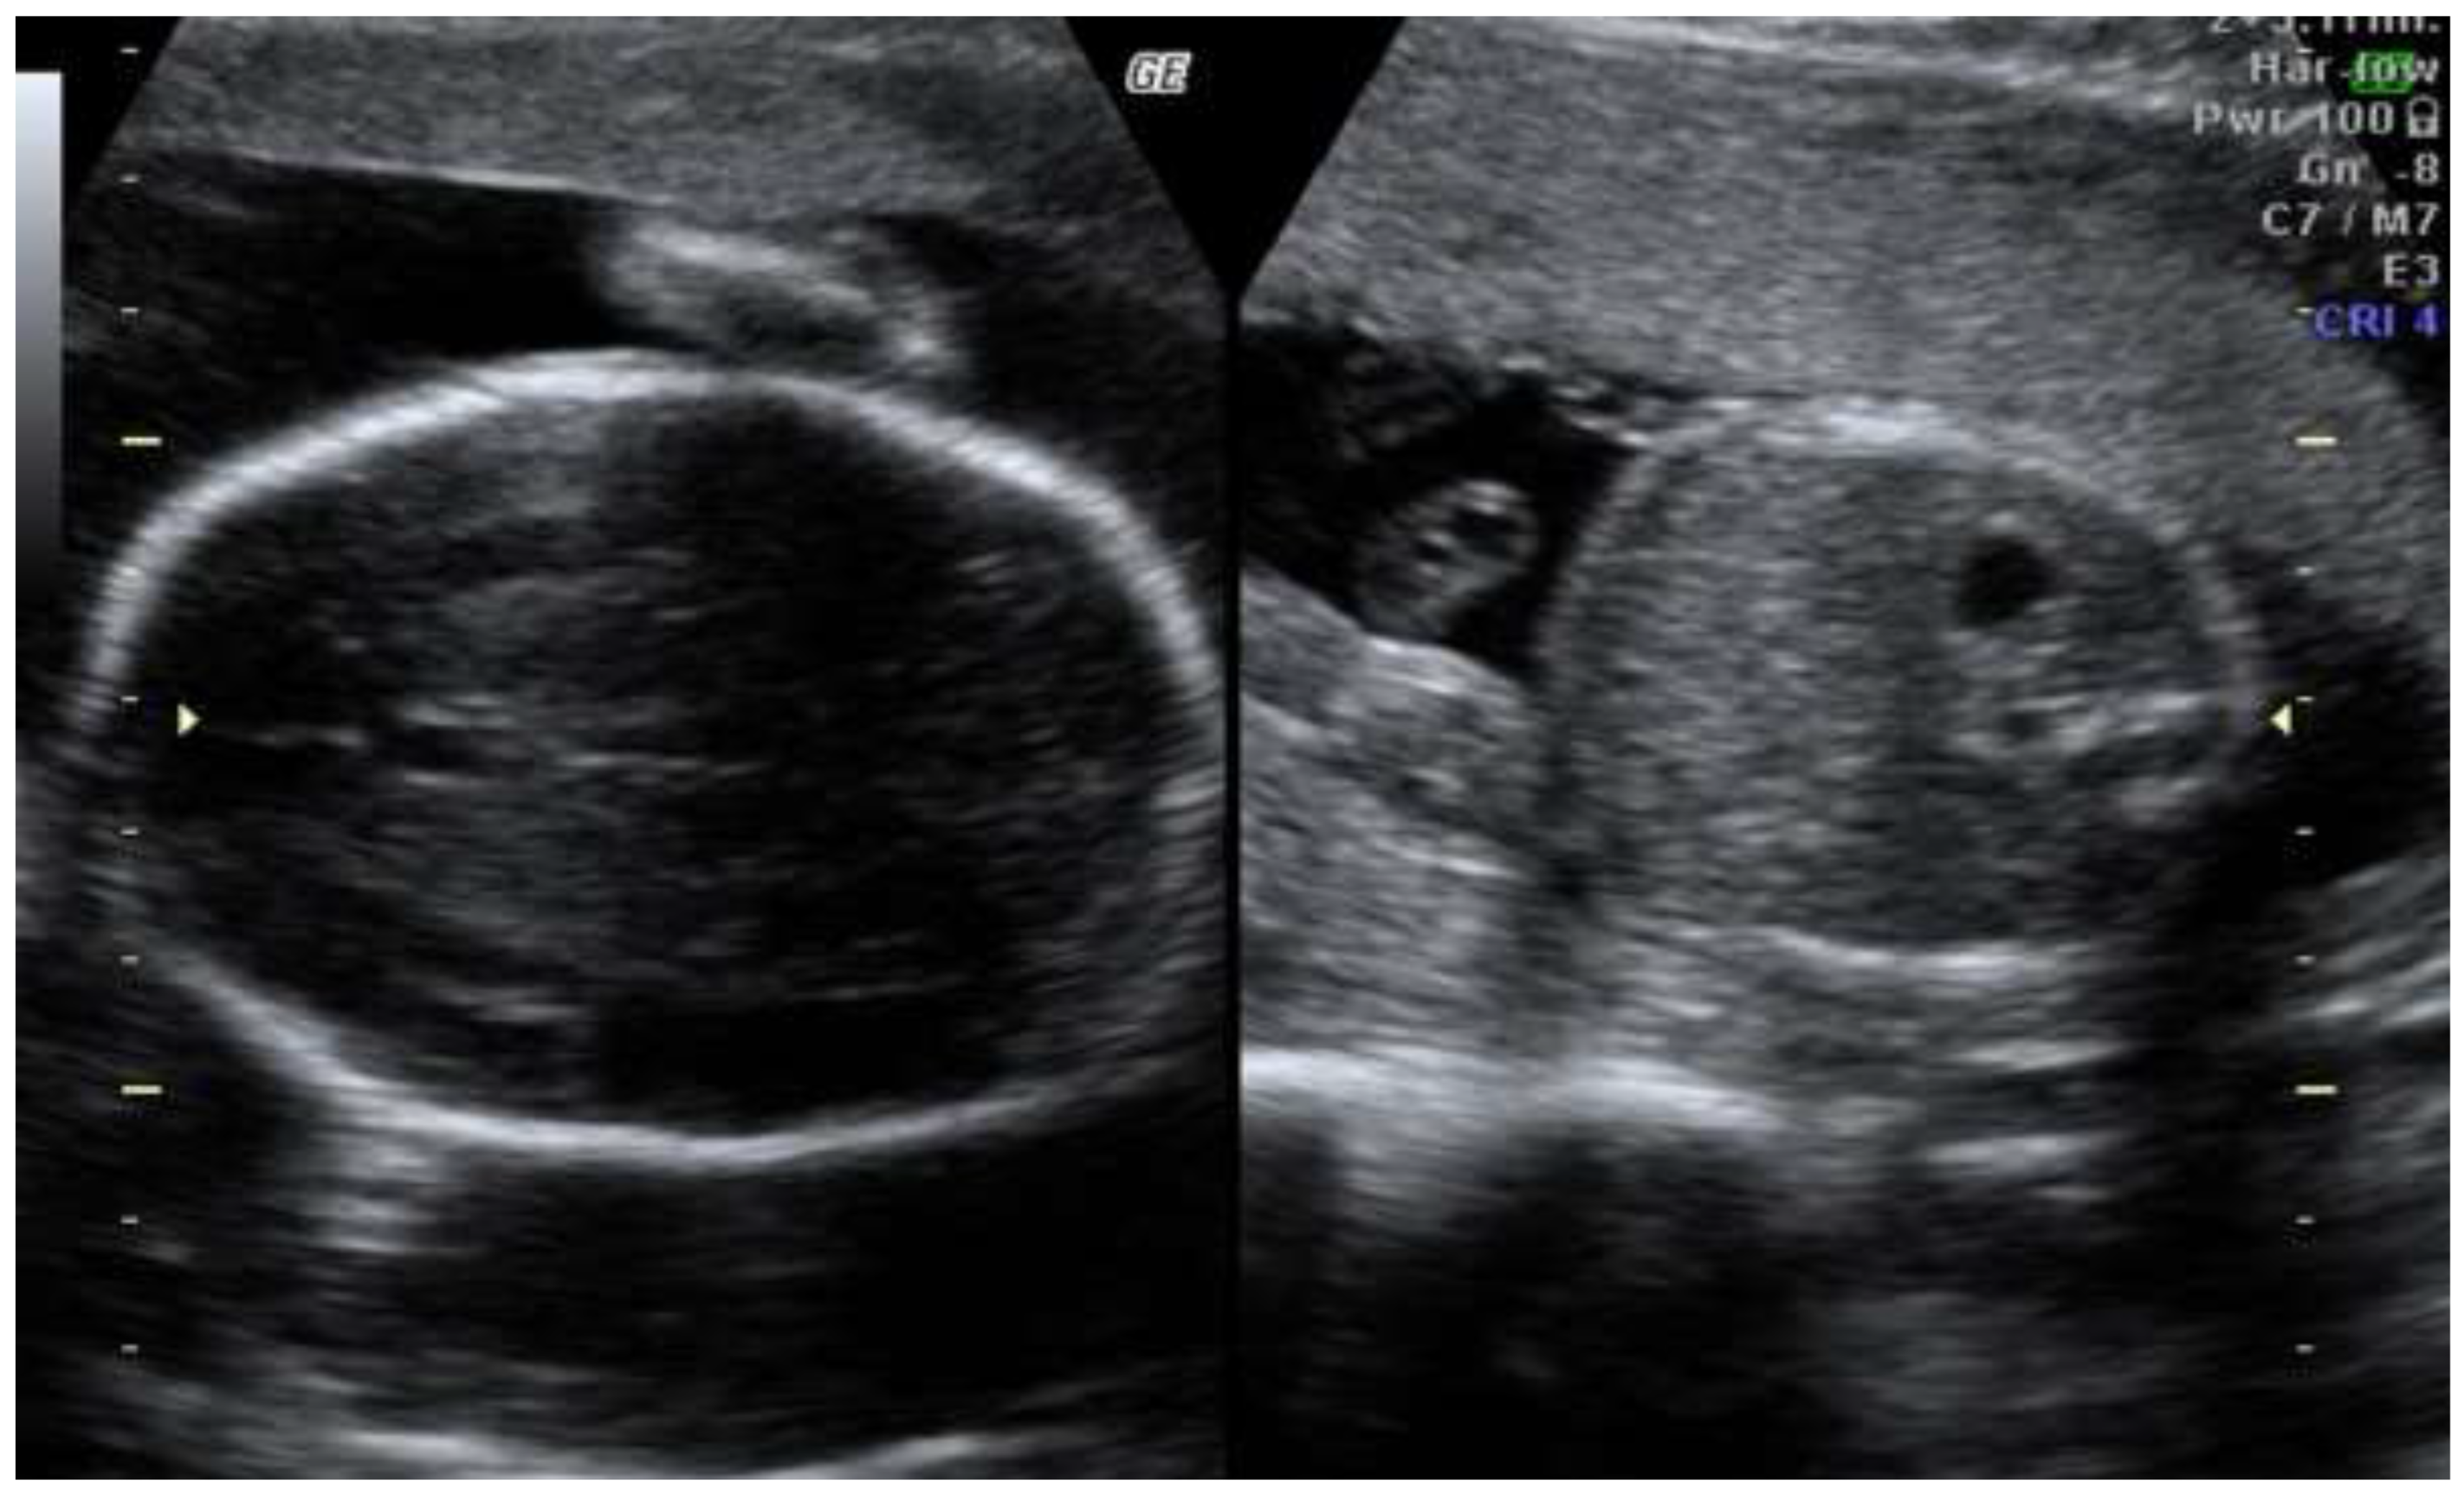

The second trimester scan revealed progression of asymmetric fetal growth restriction (Figure 2)

Figure 2. Second trimester scan revealing progression of the asymetric growth restriction.